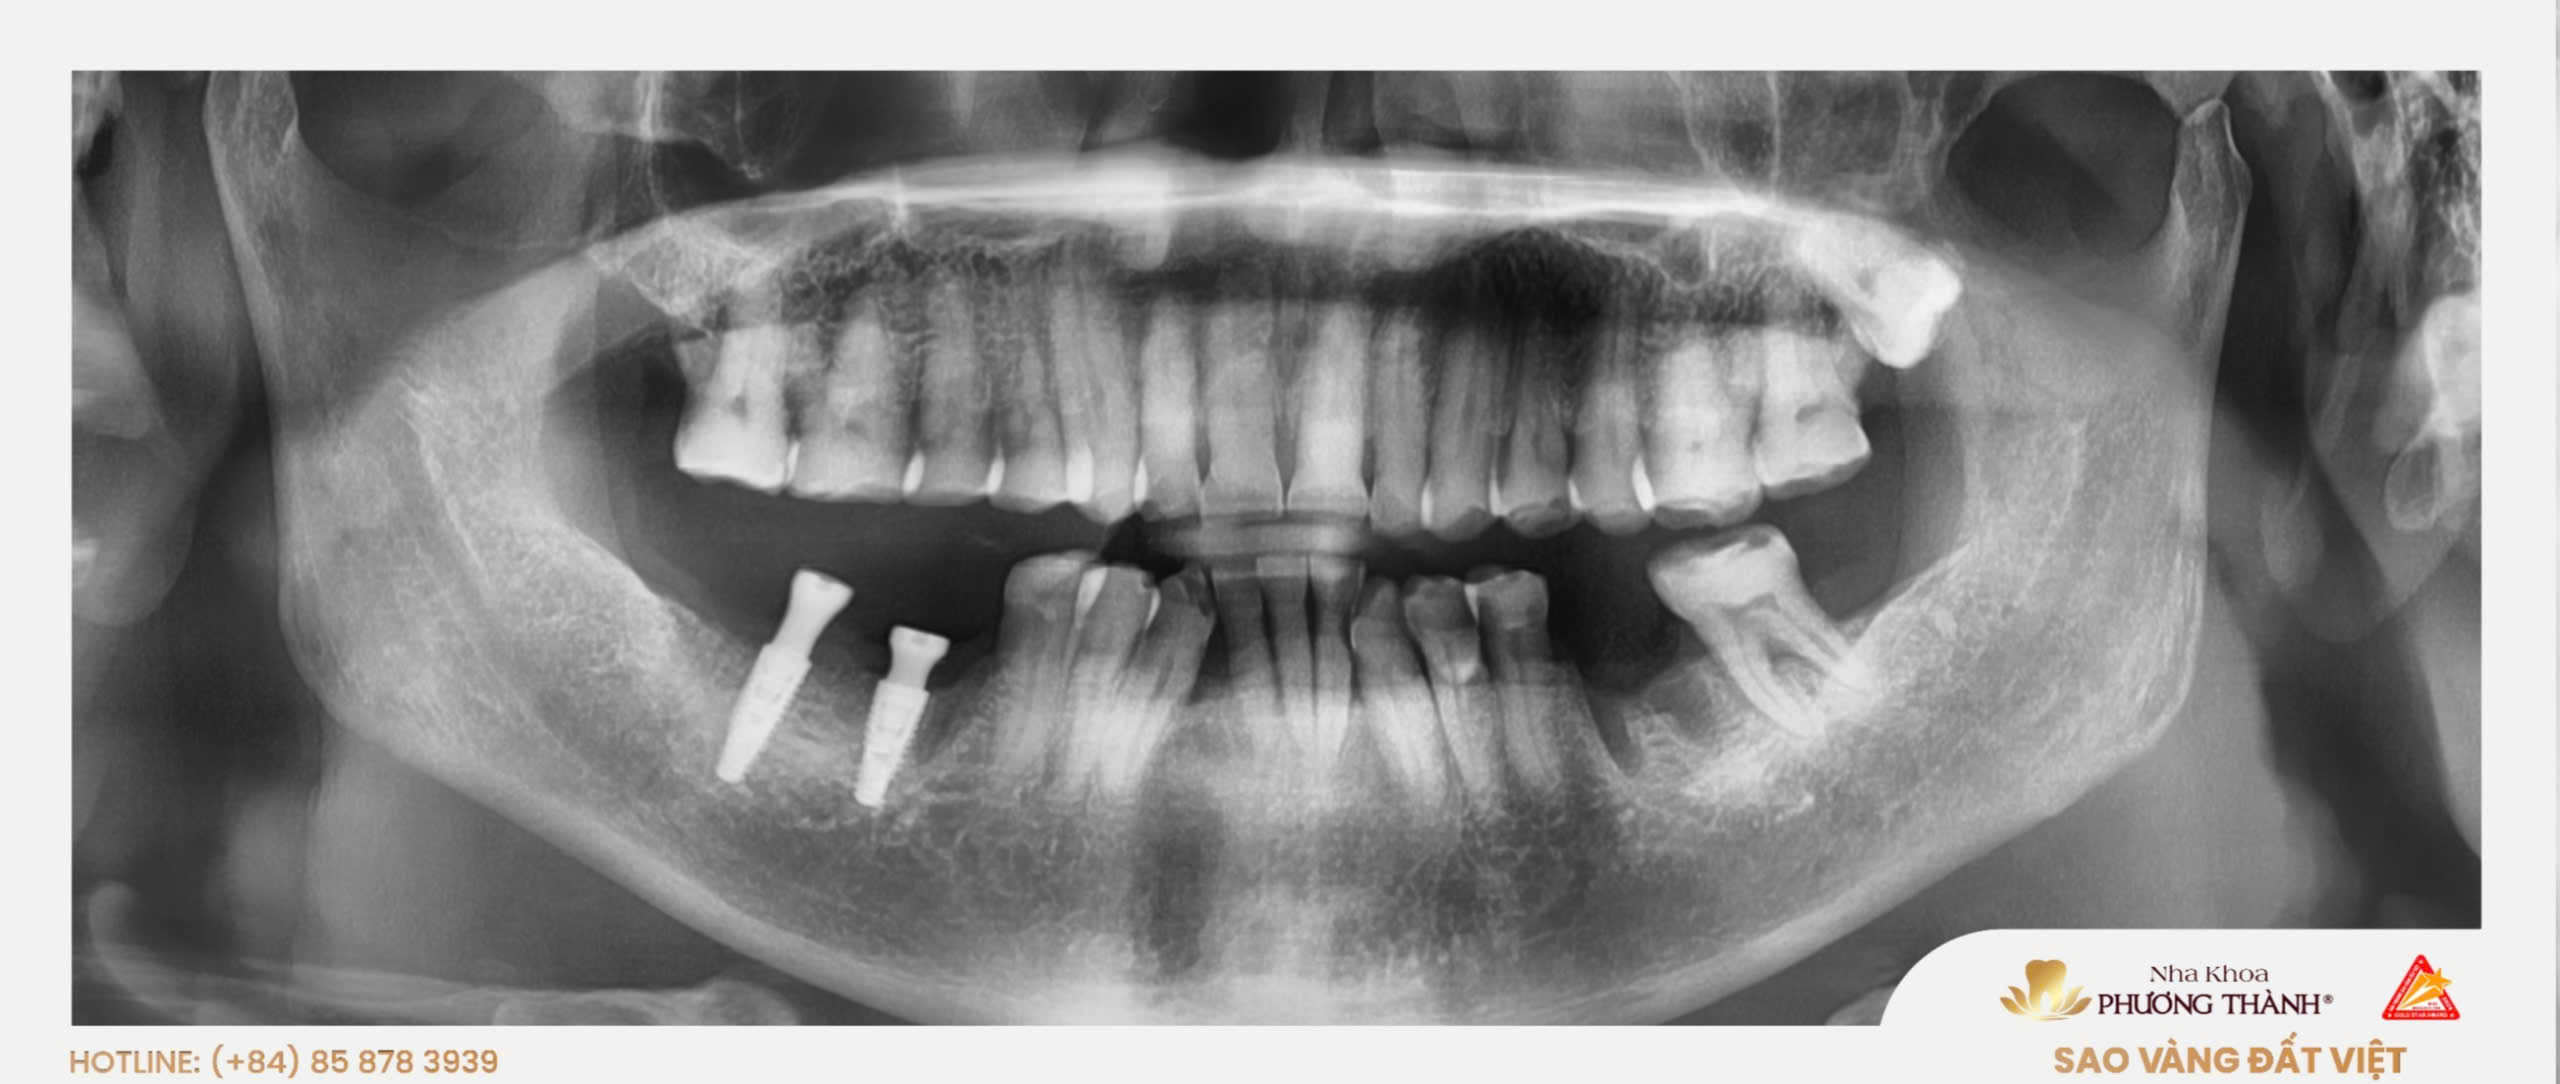

Khách hàng đến với Nha khoa Phương Thành trong tình trạng mất răng, ảnh hưởng đến cả chức năng ăn nhai lẫn sự tự tin trong sinh hoạt hằng ngày. Sau khi thăm khám, chụp phim và đánh giá tình trạng xương hàm, bác sĩ đã tư vấn phương án cấy ghép Implant nhằm phục hồi răng mất theo hướng ổn định, độc lập và bảo tồn cấu trúc răng thật.

Trong trường hợp này, khách hàng được chỉ định cấy ghép 2 trụ Implant Thụy Sĩ sau khi đã được kiểm tra kỹ về vị trí mất răng, chất lượng xương hàm và điều kiện phục hình. Đây là bước quan trọng giúp bác sĩ xây dựng kế hoạch điều trị phù hợp với tình trạng thực tế của từng người.